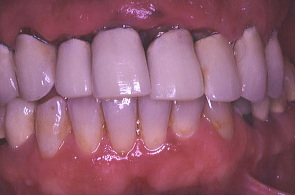

初診時の口の中の状態、歯ぐきは赤く腫れている。特に上の歯肉全体が浮腫して歯肉の締まりがなくなっている。

歯科医院指導の下、患者の熱心な歯磨きと衛生士の機械的清掃により、初診時に比べ歯ぐきが引き締まった。